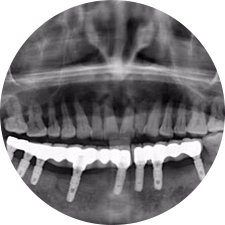

術(shù)前患者CBCT口掃1:1三維重建,模擬手術(shù)過(guò)程及預(yù)測(cè)術(shù)后治療效果,確定每顆植體植入的適合的種植位點(diǎn)、深度及角度,有效避免損傷頜骨重要解剖結(jié)構(gòu),提高手術(shù)準(zhǔn)確度與安全性。

惟德口腔種植體系是以患者感受為中心,取代傳統(tǒng)種植牙手術(shù)需要翻瓣、打孔、縫合,術(shù)前、術(shù)中、術(shù)后的繁復(fù)流程,采用3D導(dǎo)航微創(chuàng)準(zhǔn)確種植技術(shù),通過(guò)數(shù)字化CAD/CAM掃描技術(shù)獲得缺牙患者口腔數(shù)據(jù),以數(shù)據(jù)為基礎(chǔ)重建口腔模型進(jìn)行模擬種植。

術(shù)前將患者口內(nèi)的CBCT數(shù)據(jù)及咬合關(guān)系上傳到計(jì)算機(jī)中,建立1:1三維重建,模擬手術(shù)過(guò)程及預(yù)測(cè)術(shù)后治療效果,找出較佳種植位點(diǎn)、深度及角度,獲取實(shí)際種植體在頜骨內(nèi)的具體三維位置,有效避免損傷頜骨重要解剖結(jié)構(gòu),大大降低手術(shù)風(fēng)險(xiǎn),提升種植成功率。